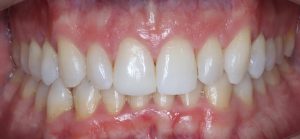

INITIAL

22 Semanas de Tratamiento